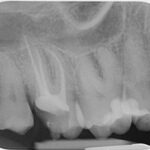

Tief zerstörter Zahn

Instrument im Wurzelkanal